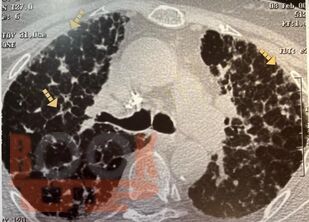

Гранулематозные заболевания легких

Гранулематозные заболевания легких : учебное пособие / И. В. Демко, Н. В. Гордеева, М. Г. Мамаева и др. - Красноярск : КрасГМУ, 2022. - 167 c. - Текст : электронный // ЭБС "Букап" : [сайт]. - URL : https://www.books-up.ru/ru/book/granulematoznye-zabolevaniya-legkih-19634258/ (дата обращения: 17.04.2026). - Режим доступа : по подписке.

Учебное пособие предназначено для врачей общей практики, участковых терапевтов, аллергологов, пульмонологов. В настоящем учебном пособии освещены принципы ведения пациентов с диссеминированными заболеваниями легких. Обсуждаются вопросы этиологии, патогенеза, диагностики, а также основные методы лечения.